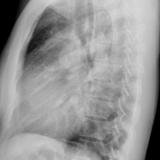

ASD 1 Lat